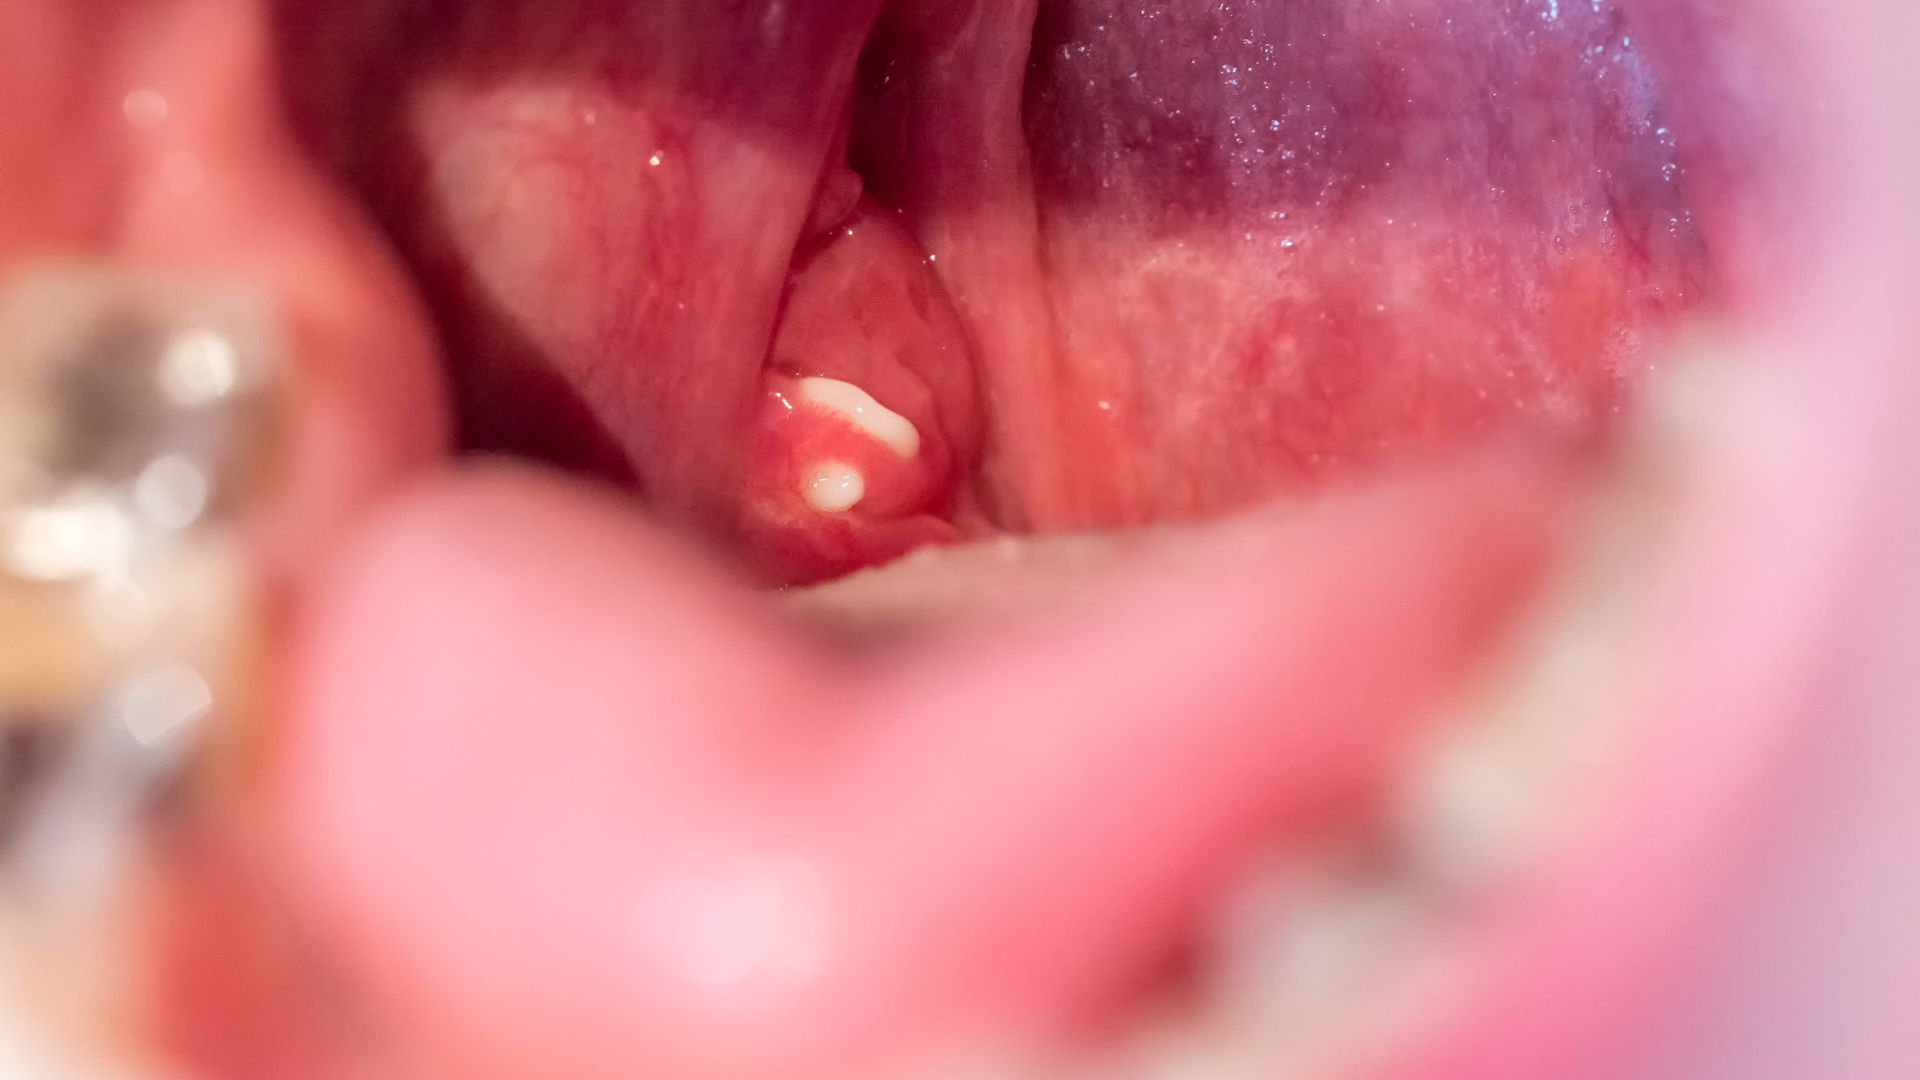

Doctor advises when to remove tonsils

MSc. Dr. Van Thi Hai Ha - Ho Chi Minh City University of Medicine and Pharmacy Hospital - advises on effective treatment and prevention of tonsillitis complications in adults.